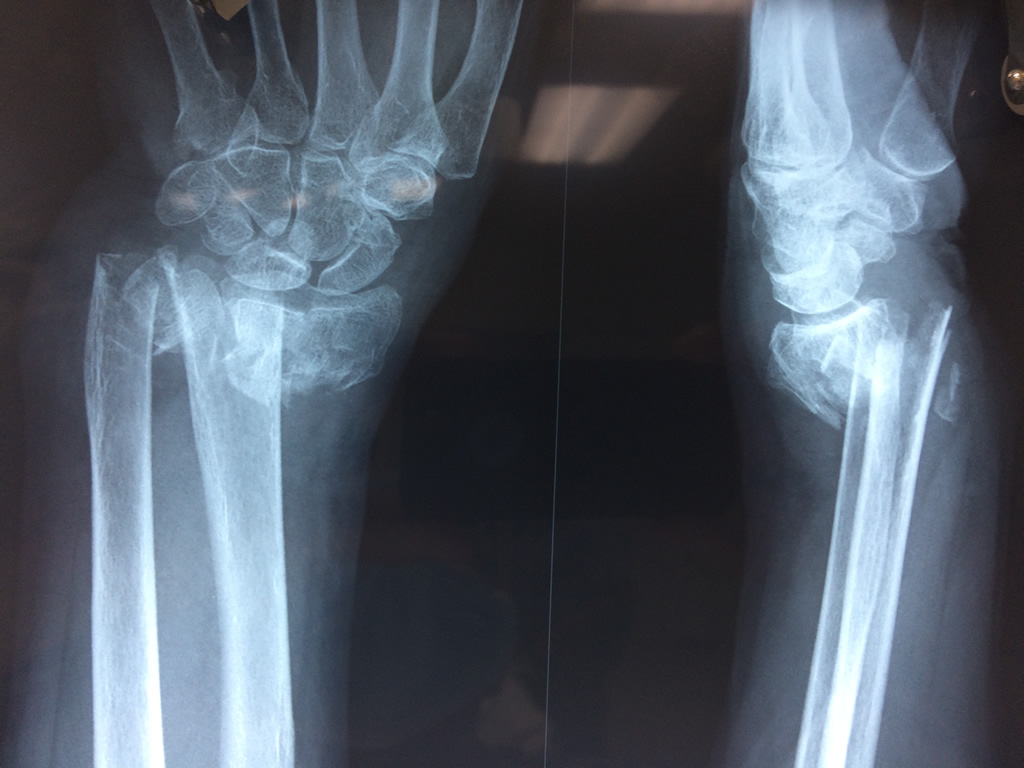

Cirugías de Codo - Cirugías de Muñecas y Manos

Los procedimientos más comunes en cirugía de la mano son aquellos destinados a reparar traumatismos, incluyendo lesiones de tendones, nervios, vasos sanguíneos, y articulaciones; huesos fracturados; y quemaduras, cortes, y otros daños de la piel.